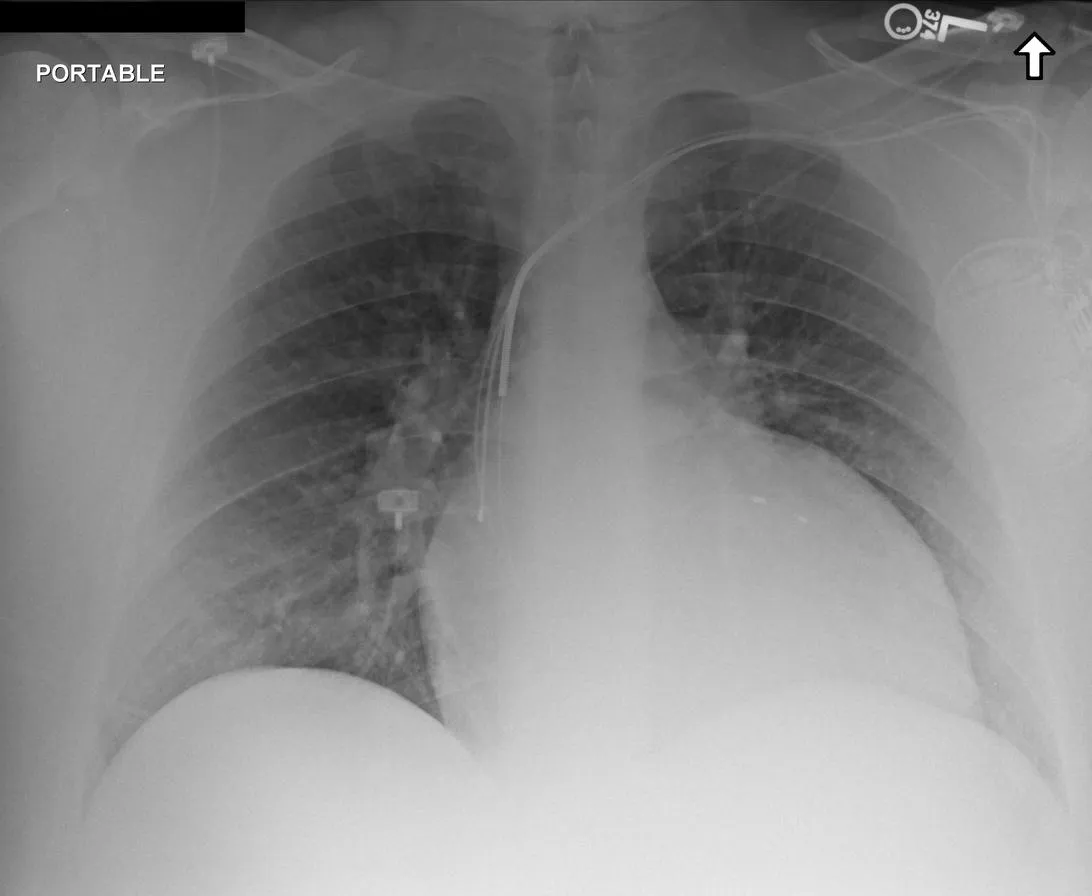

Medical grounding reasoning takes a raw image, reasons through what it observes, and outputs bounding boxes marking the abnormalities. This isn't simply helpful visualization. It's the mechanism by which reasoning becomes verifiable. Another clinician can look at the marked region and independently judge whether the finding exists.

Medical grounding reasoning marks abnormalities with bounding boxes, making diagnostic conclusions traceable and independently verifiable.

Similarly, magnification-assisted reasoning mimics how radiologists actually work. When something appears ambiguous at normal magnification, you zoom in. The model learns this as a taught skill. When uncertain about a finding, it doesn't speculate. It calls a zoom tool, examines the magnified region, and then reasons about what it observes.

Magnification-assisted reasoning shows the model analyzing an original image, calling a zoom tool to examine suspicious areas, and rendering conclusions based on the magnified view.

These capabilities matter because they bridge the gap between "the model gave an answer" and "I understand why and can verify it." Without grounding and magnification, even correct diagnoses feel like black boxes. With them, the reasoning becomes transparent and subject to clinical judgment.